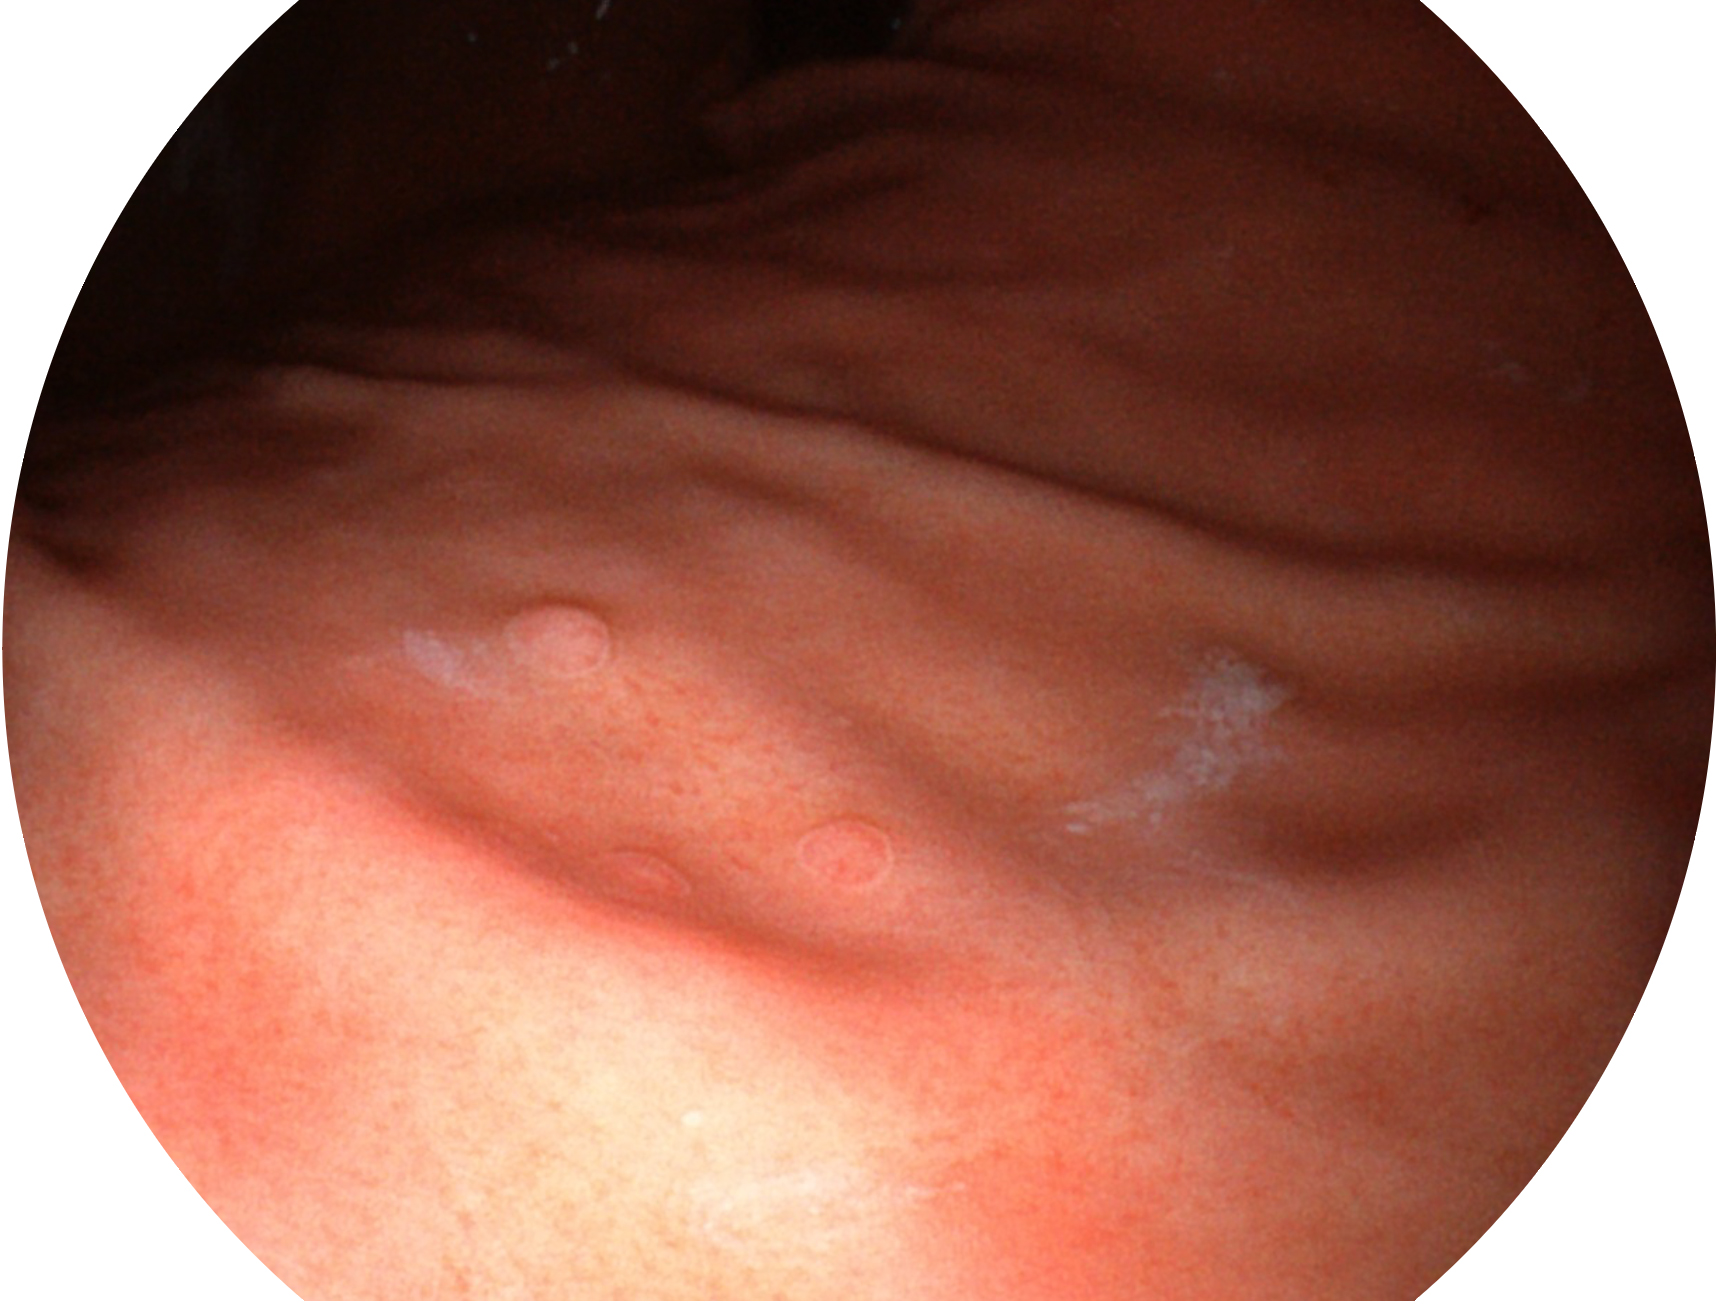

MILE米乐集团官网新开发的内镜染色技术,主要是基于多波长LED 光源的开发,VLS-55Q 四波长LED 光源是由四个不同颜色的LED光按照相应照明模式所规定的特定发光比例进行合束后形成,合束后形成的照明光的光谱由红光、绿光、蓝光及蓝紫光这四个不同的波段范围构成。具有更高光谱自由度,通过光谱比例的控制,实现了聚谱成像技术,英文全称为“Spectral Focused Imaging, SFI”,缩写为“SFI”和光电复合染色成像技术,英文全称为“Versatile Intelligent Staining Technology, VIST”,缩写为“VIST”。